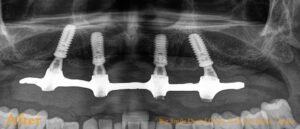

We then took measurements to create a diagnostic model, captured photographs, did scaling on lower arch and used virtual 3D planning to determine the optimal placement and size for the implants. On next day, following routine blood tests for the surgical procedure, we proceeded with the implant placement after removing his remaining upper teeth. Remarkably, on the same day, we were able to provide him with fixed temporary teeth. This 4-hour procedure was painless and uneventful, leaving him comfortable and with a full set of teeth.

Fig: Immediately after implant placement, Temporary immediate denture and Post- operative photograph immediately after surgery.